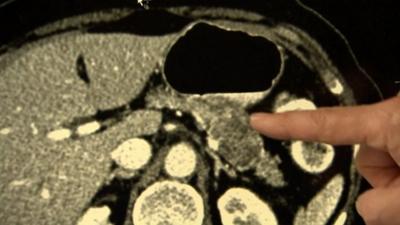

Surgeon Ashley Dennison, at Leicester General Hospital, said the long-term survival rate for pancreatic cancer had not changed much in over 30 years.